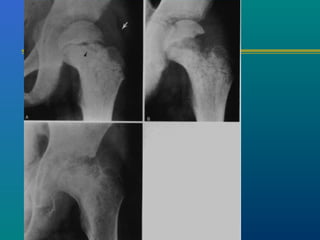

PERTHES DISEASE

Common problem

4 – 12 years of age

INVESTIGATIONS

X-ray --- AP & FROG LEG

LATERAL

Sclerosis of the epiphysis

Collapse of the epiphysis

Subchondral fracture

CATERALLCATERALL CLASSIFICATIONCLASSIFICATION

 Group I only ant. part of

epiphysis involved

 Group II ¼ to ½ involved

 Group III upto ¾ involved

head at risk sign

 Group IV whole epiphysis

sequestrated